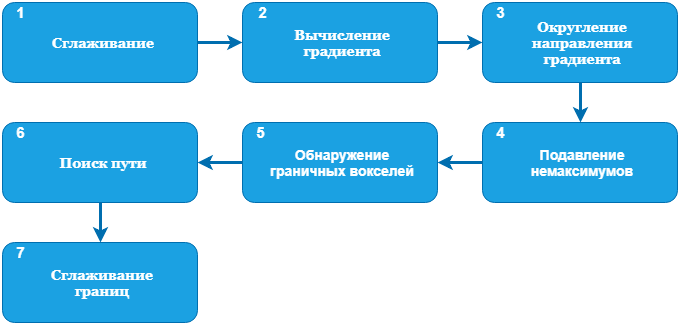

Чтобы оценить сужение сосуда, нам нужно знать просвет сосуда или его внутреннюю границу. Для этого нужно как минимум обнаружить весь кальций. Также мы находим внешнюю границу, потому что она дает возможность оценить толщину стенки, что также полезно. Для начала давайте взглянем на полную схему обнаружения границ, а затем подробно разберем каждый этап:

Для обнаружения границ сосуда используется классический подход (edge detection by gradient) совместно с поиском пути. Схема:

1. Применяем сглаживание Гаусса с небольшим значением

Далее нам потребуются направление градиента

3. Направление градиента переводим в градусы или радианы:

4. Выполняем подавление немаксимумов. Если значение градиента

5. Все оставшиеся воксели считаются границами. На основании значения градиента, порога кальция (который доступен не сразу) и близости к “вертикальному” центру, каждой точке присваивается определенная стоимость (чем ярче воксель, тем выше его приоритет при поиске пути):

В таком виде границы сосуда уже практически однозначно определены.

6, 7. Чтобы построить границы воспользуемся поиском пути. В качестве начальной и конечной берутся ближайшие крайние точки с наименьшей стоимостью. Для поиска пути используется обычный поиск в ширину, который выбирает граничные точки с наименьшей стоимостью. Также доступны прыжки, но цена их высока. Верхняя и нижняя границы сосуда ищутся раздельно, и после к ним применяется сглаживание: